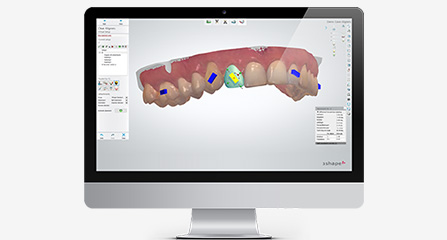

麦芽口腔着眼于全链条的数字化诊疗解决方案,与德国Kavo、瑞典Nobel、韩国奥齿泰、中国康泰健等国际知名齿科品牌合作,建立“深圳数字化口腔联盟”,应用全数字化口腔模式,从CBCT数据提取、AI口扫取模、AI智能口腔体检、数字化分析模拟与方案设计、3D打印、CAD/CAM椅旁加工以及手术模拟导航等,全流程打通数字化口腔精确诊疗的各个环节,实现麦芽数字化口腔诊疗体系新升级。

智能口扫取模 避免数据误差

数据云端整合 智能方案模拟

3D可视呈现 医患无缝沟通